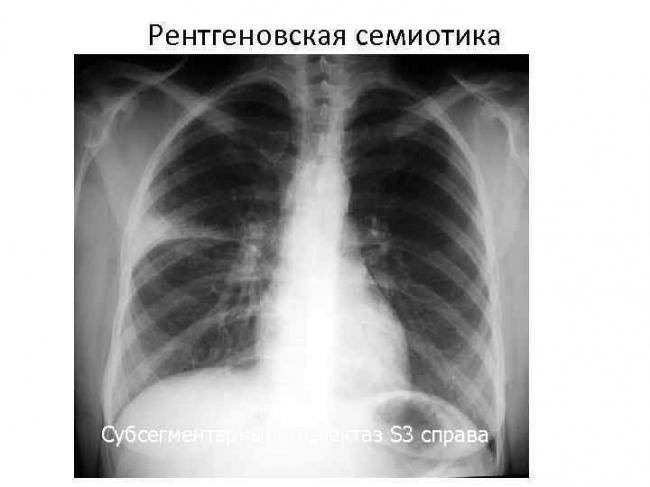

На рентгеновских снимках выявляют следующие признаки, указывающие на спадение легочной ткани:

Однородное затемнение в области поражения. Размеры тени зависят от вида ателектаза: при долевом выявляется обширное затемнение, при сегментарном — в виде клина или треугольника, расположенного вершиной к корню легкого, дольковые ателектазы множественные и похожи на очаговую пневмонию. Дистензионный ателектаз расположен низко, около диафрагмы, имеет небольшие размеры и вид поперечных полос или темных дисков. Смещение органов: при компрессионном ателектазе смещение наблюдается в здоровую сторону, так как на стороне поражения давление больше, при обтурационном, наоборот – смещение будет в сторону ателектаза, так как на стороне поражения нарастает притягивающее отрицательное давление. Подъем купола диафрагмы – это видно по расположению печени.

Помимо всего перечисленного выше, рентгеноскопия, то есть исследование «вживую», позволяет увидеть куда смещаются органы в зависимости от фазы дыхания, кашля. Это является дополнительным признаком ателектаза, помогающим выявить тип болезни.

Предварительным, рентгенологическим диагнозом является «синдром правой доли», при котором выявляется затемнение площади средней доли правого легкого.

Частое возникновение ателектаза правого легкого связано с анатомическими особенностями правого среднедолевого бронха: он узкий и длинный, поэтому часто происходит его перекрытие при патологическом процессе.